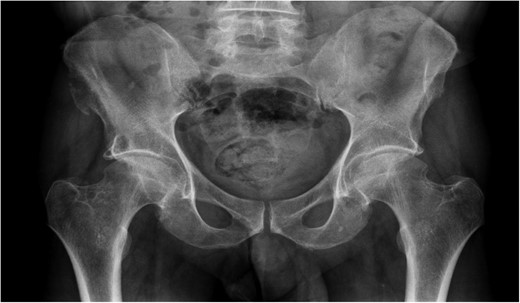

A previously fit and well 68-year-old male presented with a 6-month history of pain in the right hip. On examination this was localised to the superior area of the hip joint where a bony mass could be palpated. A pelvic radiograph was performed (Fig. 1) showing a bony exostosis on the right iliac wing. To characterise the lesion further, a pelvic Magnetic resonance imaging (MRI) scan was performed (Fig. 2). Appearances were consistent with an osteosarcoma and referral to the local sarcoma centre for histological investigation was made. Surprisingly, sampling from biopsy showed invasive well-differentiated adenocarcinoma. Staging computed tomography (CT) scanning did not reveal a primary source for the tumour but did identify thickening of the descending colon (Fig. 3) and lymphadenopathy involving the left supraclavicular, thoracic, paravertebral, retro-crurual and right inguinal regions. There was no evidence of tumour in the liver, lung or other parts of the skeleton. Subsequently, colonoscopy identified the thickened lesion as a hepatic flexure adenocarcinoma (Fig. 4). Biopsy at the time of endoscopy revealed the lesion at the hip to be a metastasis.

Intraluminal images demonstrating a lesion at the hepatic flexure.